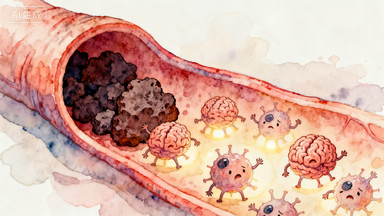

当脑梗发生时

我们的大脑正在经历一场可怕的“干旱”

而急性脑梗死取栓手术

就是一支精准的“抢修队”

其任务是在黄金时间内

快速打通被堵塞的“生命河道”

拯救濒临死亡的脑细胞

很多人对取栓手术感到陌生,刘俊中主任用通俗的比喻解释:“大多数脑梗死都是大脑里的大血管被血栓(血块)堵住了。”

“我们的大脑就像身体的总司令部,需要血液持续输送氧气和营养,而大血管就是通往总司令部的‘主干道’,血栓则像一块巨大的‘石头’,把主干道彻底堵死了。”

“主干道” 被堵,下游的脑组织会因为缺血缺氧迅速坏死,对应的手脚活动、说话等功能就会丧失。

而取栓手术,就是医生通过微创的方式,直接把堵在血管里的血栓取出来,快速打通被堵塞的 “生命河道”,拯救濒临死亡的脑细胞。